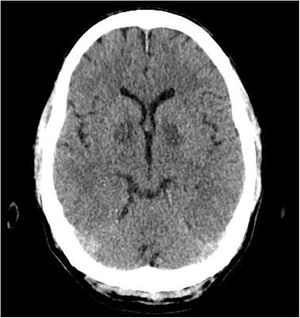

A 53-year-old male was admitted to the Intensive Care Unit with cardiogenic shock secondary to severe carbon monoxide poisoning. Treatment was started with 100% O2 due to initial carboxyhemoglobin levels of 25%. Echocardiography was performed due to sustained hypotension despite resuscitation and vasoactive drugs (Appendix B enclosed video, left), revealing severe biventricular dysfunction with an estimated cardiac output of 1.8 L/min that gradually recovered in the subsequent 48 h with inotropic support in the form of dobutamine (Appendix B enclosed video, right). The initial ECG tracing evidenced no known right bundle block (Fig. 1, image A) that reverted after the first 24 h, evolving towards subendocardial injury on the anterolateral surface and posterior ischemia in those territories (Fig. 1, images B and C). The brain CT scan evidenced symmetrical bilateral hypodensity in the globus pallidus (Fig. 2) – this image being characteristic of carbon monoxide poisoning due to the high iron content and high sensitivity to hypotension.